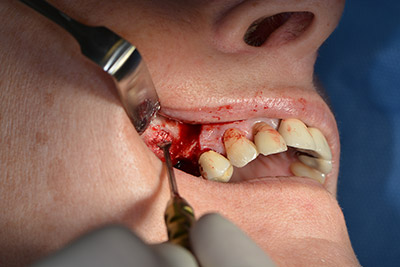

Die klassische Schnittführung (krestal, Entlastung bukkal) und das Präparieren des Mukoperiostlappens erlauben eine gute Übersicht.

In diesem Fall werden Sky Implantate (bredent) verwendet, deren chirurgisches Protokoll die Pilotbohrung mit etwa 1.200/min vorschreibt (Abb. 9).